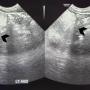

Abdominal ultrasound showed a large lobulated hyperechoic mass occupying abdomen and pelvis (black arrowhead)

Case Report Page 824 - 828

Paediatric Mesenteric Lipoblastoma: A Remarkable Rarity